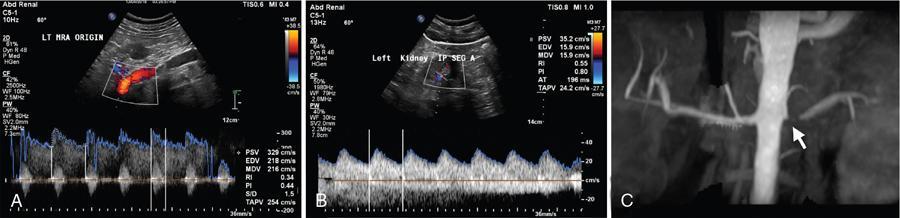

• Doppler evaluation of abdominal aorta and renal arteries: Abdominal aorta is assessed for its size, any atherosclerotic changes and PSV in its prerenal segment. Doppler assessment of bilateral main renal arteries is done at its origin, proximal and distal segments. Doppler assessment of intrarenal branches should also be done. Colour and spectral Doppler assessment of RAS is shown in Fig. 10.18.1.3.

• There are various direct and indirect Doppler signs in RAS as described below:

• Direct signs at the site of stenosis:

• Renal artery PSV: >180 cm/s

• Renal artery PSV to abdominal aorta PSV ratio: >3.5

• Colour aliasing at the site of stenosis (indicating turbulence of flow)

• Absent colour and spectral signals in case of complete occlusion

• Indirect signs distal to the site of stenosis:

• Pulsusparvus et tardus waveform (low velocity, sluggish flow)

• Increased AT (time to peak systole): >70 ms

• Decreased AI (slope of systolic upstroke): <300 cm/s2

• Sensitivity and specificity of Doppler in detecting RAS are 95% and 90% using renal artery PSV of >180 cm/s as criteria. Therefore, renal artery Doppler serves as screening modality in evaluation of newly diagnosed hypertension to rule out RAS. Recommended reporting format of renal Doppler assessment is provided in Appendix I.

Fig. 10.18.1.3 Doppler image for renal artery stenosis.